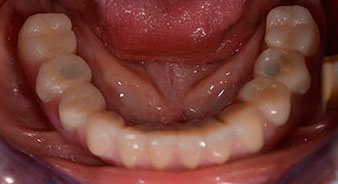

Die 64-jährige Patientin wurde mit einer Unterkiefer-Restbezahnung 38, 33 und 43 und einer klammerbefestigten Interimsprothese im Unterkiefer vorstellig (Abb. 1 und 2).